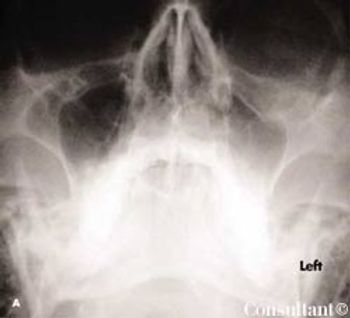

Redness, irritation, and diplopia developedover 2 to 3 weeks in a 55-yearoldman’s left eye (A). The injectionworsened and was unresponsive toeye drops. Ptosis, mild proptosis, andelevated intraocular pressure developed.A bruit was auscultated overthe affected eye.